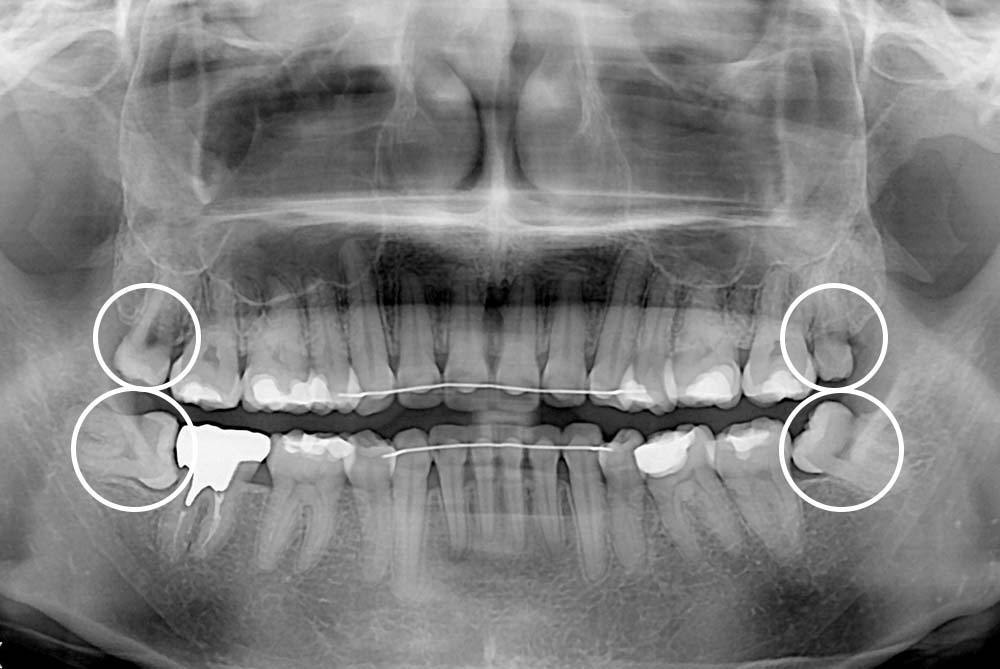

[사랑니] 매복 사랑니 발치

치료후 : 2019-08-01

세종치과는 구강악안면외과학 박사이신 원장님이 발치하는 치과입니다.